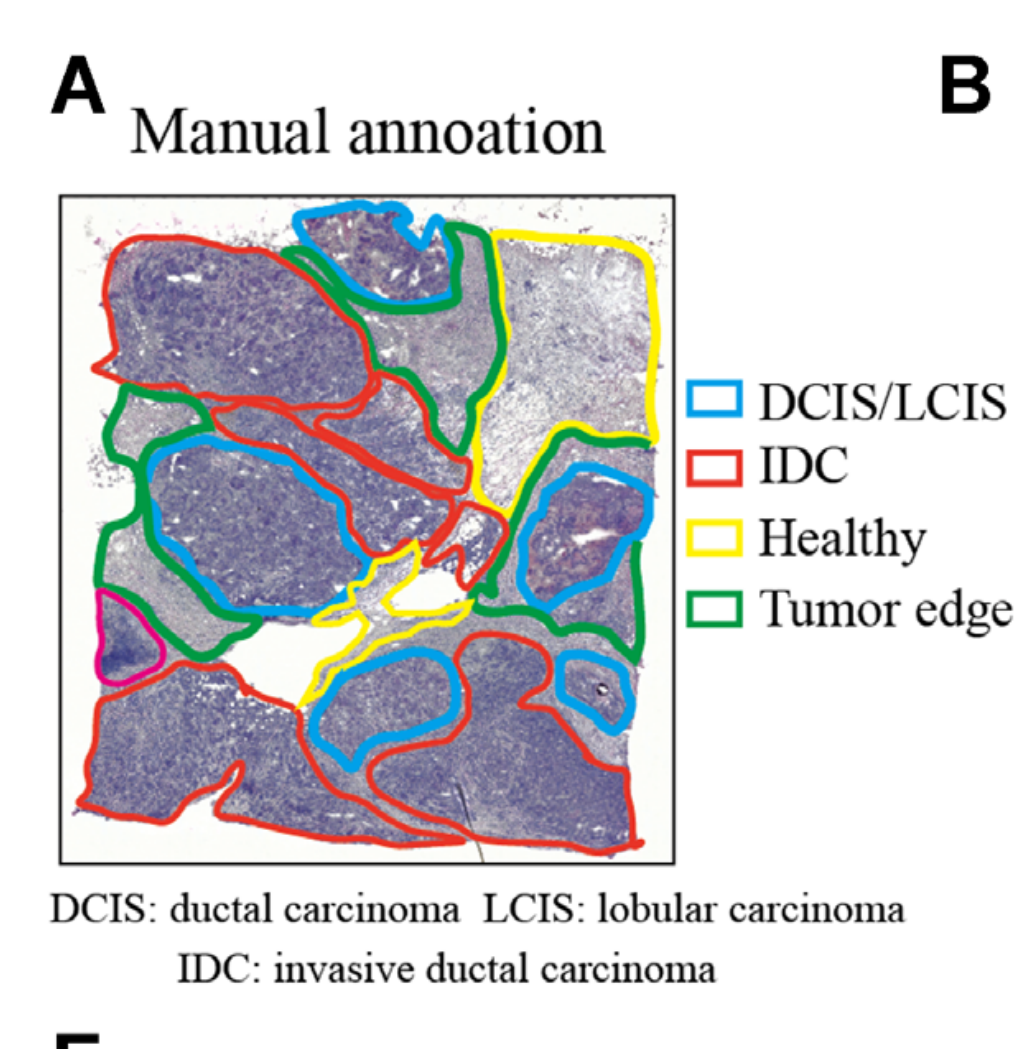

Jiang X. et al. - 2024

How are pathologist-defined tissue regions distributed across a cancer tissue section?

Partial

Histological image

Highlighting

None (Item-level)